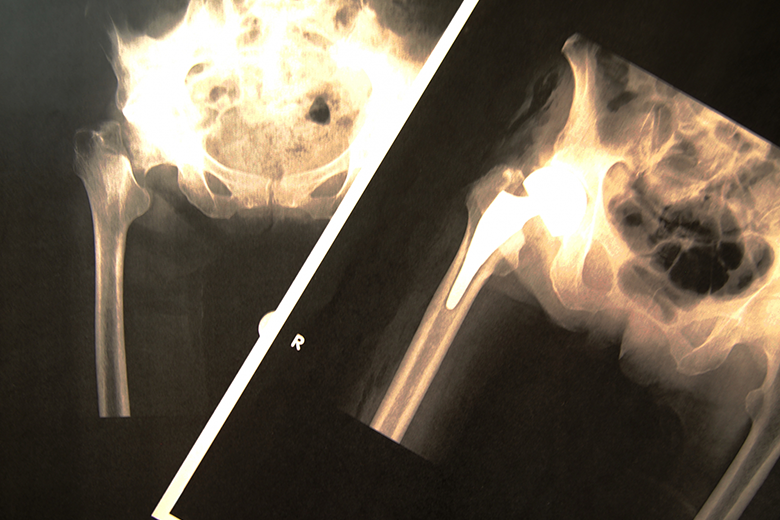

「MRIを撮ったけれど『異常は見当たりません』と言われた」

「ヘルニアと診断され手術まで受けたのに、期待したほど改善しなかった」

画像検査で原因が特定できる腰痛は、全体のわずか15%程度。

残りの約85%は「非特異的腰痛」と呼ばれ、CTやMRIなどの検査でも異常が見つからないケースなのです。